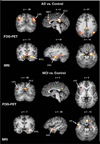

Alzheimer's disease (AD) is a progressive age-related neurodegenerative disease. At the time of clinical manifestation of dementia, significant irreversible brain damage is already present, rendering the diagnosis of AD at early stages of the disease an urgent prerequisite for therapeutic treatment to halt, or at least slow, disease progression. In this review, we discuss various neuroimaging measures that are proving to have potential value as biomarkers of AD pathology for the detection and prediction of AD before the onset of dementia. Recent studies that have identified AD-like structural and functional brain changes in elderly people who are cognitively within the normal range or who have mild cognitive impairment (MCI) are discussed. A dynamic sequence model of changes that occur in neuroimaging markers during the different disease stages is presented and the predictive value of multimodal neuroimaging for AD dementia is considered.